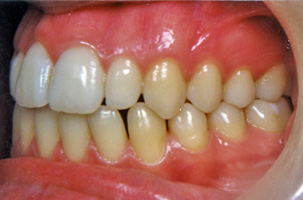

Προβλήματα λόγω της κακής θέσης των γνάθων μεταξύ τους μπορούν με την κατάλληλη ορθοδοντική μετακίνηση των δοντιών να καμουφλαριστούν και να επιτευχτεί μια αποδεκτή σύγκλειση παρά την υπάρχουσα σκελετική ανωμαλία. Παρόλα αυτά, όταν οι διαφορές μεγέθους ή/και οι σχετικές σχέσεις των γνάθων μεταξύ τους είναι έντονες, δεν είναι δυνατή η διόρθωση αποκλειστικά με την ορθοδοντική θεραπεία. Σ’ αυτες τις περιπτώσεις η ορθογναθική χειρουργική είναι απαραίτητη παράλληλα με την ορθοδοντική θεραπεία. Σε μεικτά προβλήματα όπου εμπλέκονται τόσο τα δόντια όσο και ο σκελετός, δεν είναι δυνατόν η ορθογναθική χειρουργική να αντικαταστήσει την ορθοδοντική, αλλά ούτε και η ορθοδοντική μόνη της μπορεί να διευθετήσει σωστά το συνολικό πρόβλημα. Για την αντιμετώπιση μεικτών προβλημάτων υπάρχει συγκεκριμένο πρωτόκολλο συνεργασίας. Ο ορθοδοντικός και ο γναθοχειρουργός μετά από κοινό έλεγχο του ασθενούς παίρνουν τις διαγνωστικές καταγραφές (εκμαγεία, ακτινογραφίες, φωτογραφίες) και αφού μελετήσουν το πρόβλημα, καταστρώνουν το σχέδιο θεραπείας και ορίζουν τις αρμοδιότητες των δυο ειδικοτήτων. Η θεραπεία κατά κανόνα έχει τρεις φάσεις:

1. Προχειρουργική ορθοδοντική:

Ο ορθοδοντικός καλείται να φέρει τα δόντια της κάθε γνάθου σε θέσεις τέτοιες ώστε μετά το χειρουργείο που θα ακολουθήσει, να επιτευχτεί μια ισορροπημένη σύγκλειση. Η διάρκεια της προχειρουργικής ορθοδοντικής θεραπείας είναι δυνατόν να ποικίλλει κατά περίπτωση από 12 έως 24 μήνες.